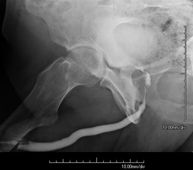

Procediment que permet, mitjançant l'ús de raigs X, i després d'injectar un contrast a l'interior de l'articulació, detectar lesions d'aquestes articulacions (cartílag, os, tendons, etc. ) segons la distribució del contrast. - RX Pelvis

Procediment que usa els raigs X a través de la qual s'obtenen imatges de la pelvis per al seu estudi, especialment dels ossos pèlvics. - RX Edat òssia